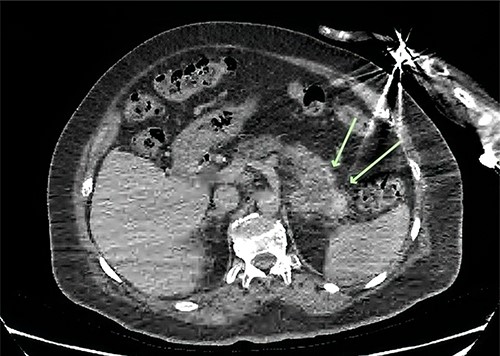

An X-ray of the right humerus demonstrated a lytic lesion in the proximal humeral diaphysis with metastatic features (Fig. 1a). Subsequent computed tomography (CT) of the right humerus demonstrated a medullary metastasis at high risk of pathological fracture (Fig. 1b). Further imaging with CT chest–abdomen–pelvis demonstrated a necrotic mass in the tail of the pancreas (Fig. 2) with direct extension into the left adrenal gland and suspected liver metastases.

Axial CT of the abdomen demonstrating a necrotic mass centred in the tail of the pancreas measuring 57 × 43 mm (green arrows).